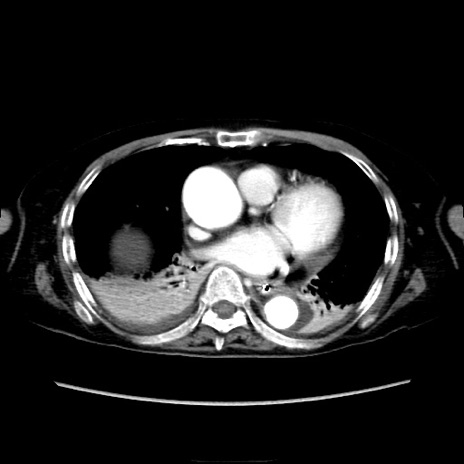

症例40(横断像)

【症例】90歳代女性

【主訴】腹痛・嘔吐

【現病歴】 食欲低下、嘔吐があり昨日他院受診。肺炎と診断され入院となる。入院後より腹部全体に圧痛あり。胃管留置され経過みていたが、症状持続するため、

当院転院となる。

【既往歴】胸椎圧迫骨折、胆石症

【身体所見】腹部:中央に激痛あり、圧痛あり、反跳痛不明

【データ】WBC 17100、CRP 18.82

横断像